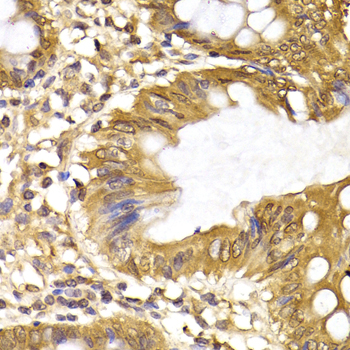

• A6246: image 2

Immunohistochemistry of paraffin-embedded rat pancreas using IRF6 antibody at dilution of 1:200 (400x lens).